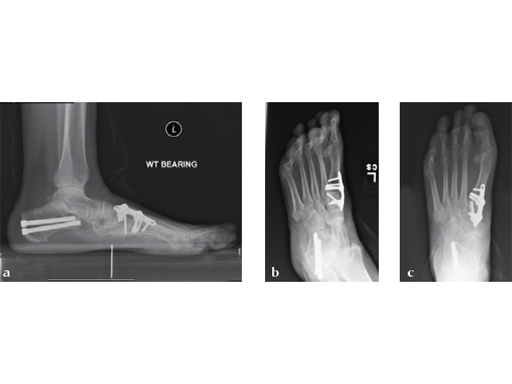

Case 2: First MTP fusion plate

A 38-year-old man presented for opinion after two attempts to fuse the big toe MTP joint. The AP view is significant for luscency at the joint line. The lateral view is notable for loosening of the hardware and malposition because of the dorsiflexion built in to the precontoured implant. Revision was planned using a 0 variable angle locking/compression hallux MTP plate.

At 10 weeks postoperatively (see Fig. 2ab) the patient had no pain with weight bearing. The lateral view demonstrates improved position of the toe using a 0angle plate.